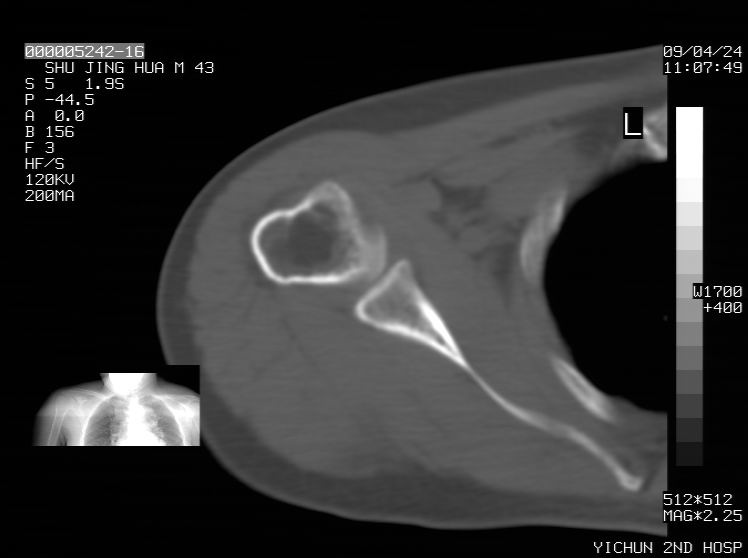

标题: CT19569:请会诊,女50岁,右肩疼痛数月 [打印本页]

标题: CT19569:请会诊,女50岁,右肩疼痛数月

钙化性肌腱炎

是指钙盐沉积在变性肌腱中的一种无菌性炎症,常见于肩关节的肩袖肌腱,引起肩部疼痛和活动受限。分为急性和慢性两种类型,急性型有肩关节突然出现急性疼痛的发作史,夜间可痛醒。